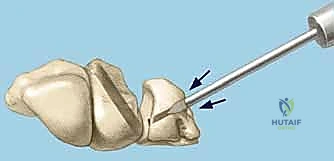

4. Lunotriquetral Reduction and K-Wire Fixation

If a direct repair is feasible, our next critical step is to anatomically reduce the lunate and triquetrum and stabilize them.

- Reduction: Gently manipulate the wrist to reduce any existing VISI deformity or dynamic instability. This often involves applying a combination of extension and radial deviation to the triquetrum while stabilizing the lunate. The goal is to restore the normal alignment and relationship between the lunate and triquetrum. Confirm reduction visually and with gentle ballottement.

- K-Wire Placement: Once reduced, we need to temporarily stabilize the joint.

- First K-wire: Insert a 0.045-inch or 0.062-inch smooth K-wire into the triquetrum at approximately a 45-degree angle, aiming towards the lunate. Advance this wire across the lunotriquetral joint and into the lunate. Ensure good purchase in both bones.

- Second K-wire: Place a second K-wire across the lunotriquetral joint, ideally starting from the lunate and crossing into the triquetrum, or vice-versa, to provide rotational stability. This creates a more rigid construct.

- Fluoroscopic Confirmation: Use intraoperative fluoroscopy to confirm anatomical reduction and optimal K-wire placement. Check both AP and lateral views. Ensure the wires are not impinging on articular surfaces or neurovascular structures.